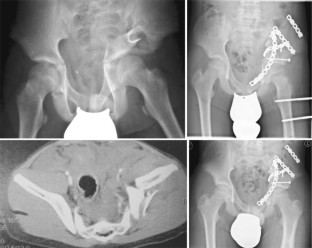

Abb. 1

Abb. 2

Abb. 3

Abb. 4